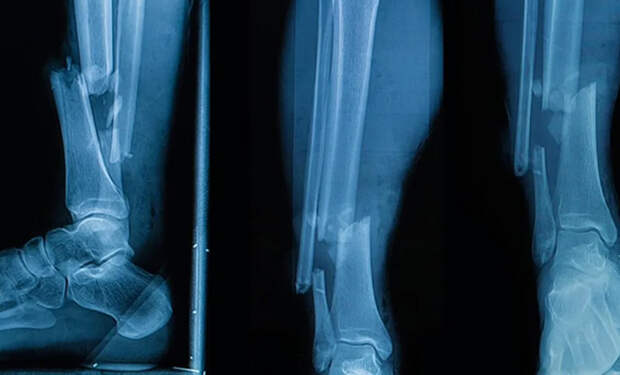

Обычно крупные переломы и дефекты кости закрывают костными трансплантатами и фиксируют пластинами, винтами и другими металлическими конструкциями. Проблема в том, что ни пластины, ни стандартные импланты не повторяют форму конкретного перелома, из-за чего страдают точность совмещения отломков и долгосрочная стабильность кости.